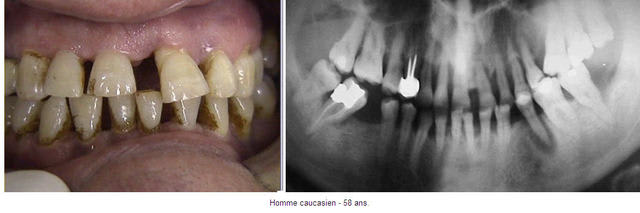

Ton expertise parodontale est impressionnante, aussi je me permets de te soumettre ce cas qui pose problème.

Si une préparation parodontale était ici effectuée, penses-tu qu’il serait envisageable de faire un traitement ODF ?

Est-ce qu’il faudra alors prévoir du torque ?

Penses-tu qu’on puisse sauver certaines de ces dents ? Quelles avulsions faut-il d’emblée réaliser ?

Admettons donc que les problèmes infectieux de cet homme de 58 ans soient résolus (on peut toujours rêver, n’est-ce pas ?).

Au vu de ces :

« > destruction osseuse ancienne

> alvéolyse verticale et horizontale

> avec des poches infra-osseuses »,

- Penses-tu qu’il serait envisageable de faire un traitement ODF ?

- Est-ce qu’il faudrait alors prévoir du torque ?

- Sur quelle dent ?

58 ans, fumeur (cela se voit), adressé par son praticien traitant pour que je remettre « dans les clous » les dents qui ont migré, lui-même s’occupe du reste..

J’ai fait la pano le jour où je l’ai vu la première fois et commencé le traitement 2 mois et demi après.